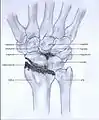

- Stage I: the osteoarthritis is only localized in the distal scaphoid and radial styloid.

Stage I